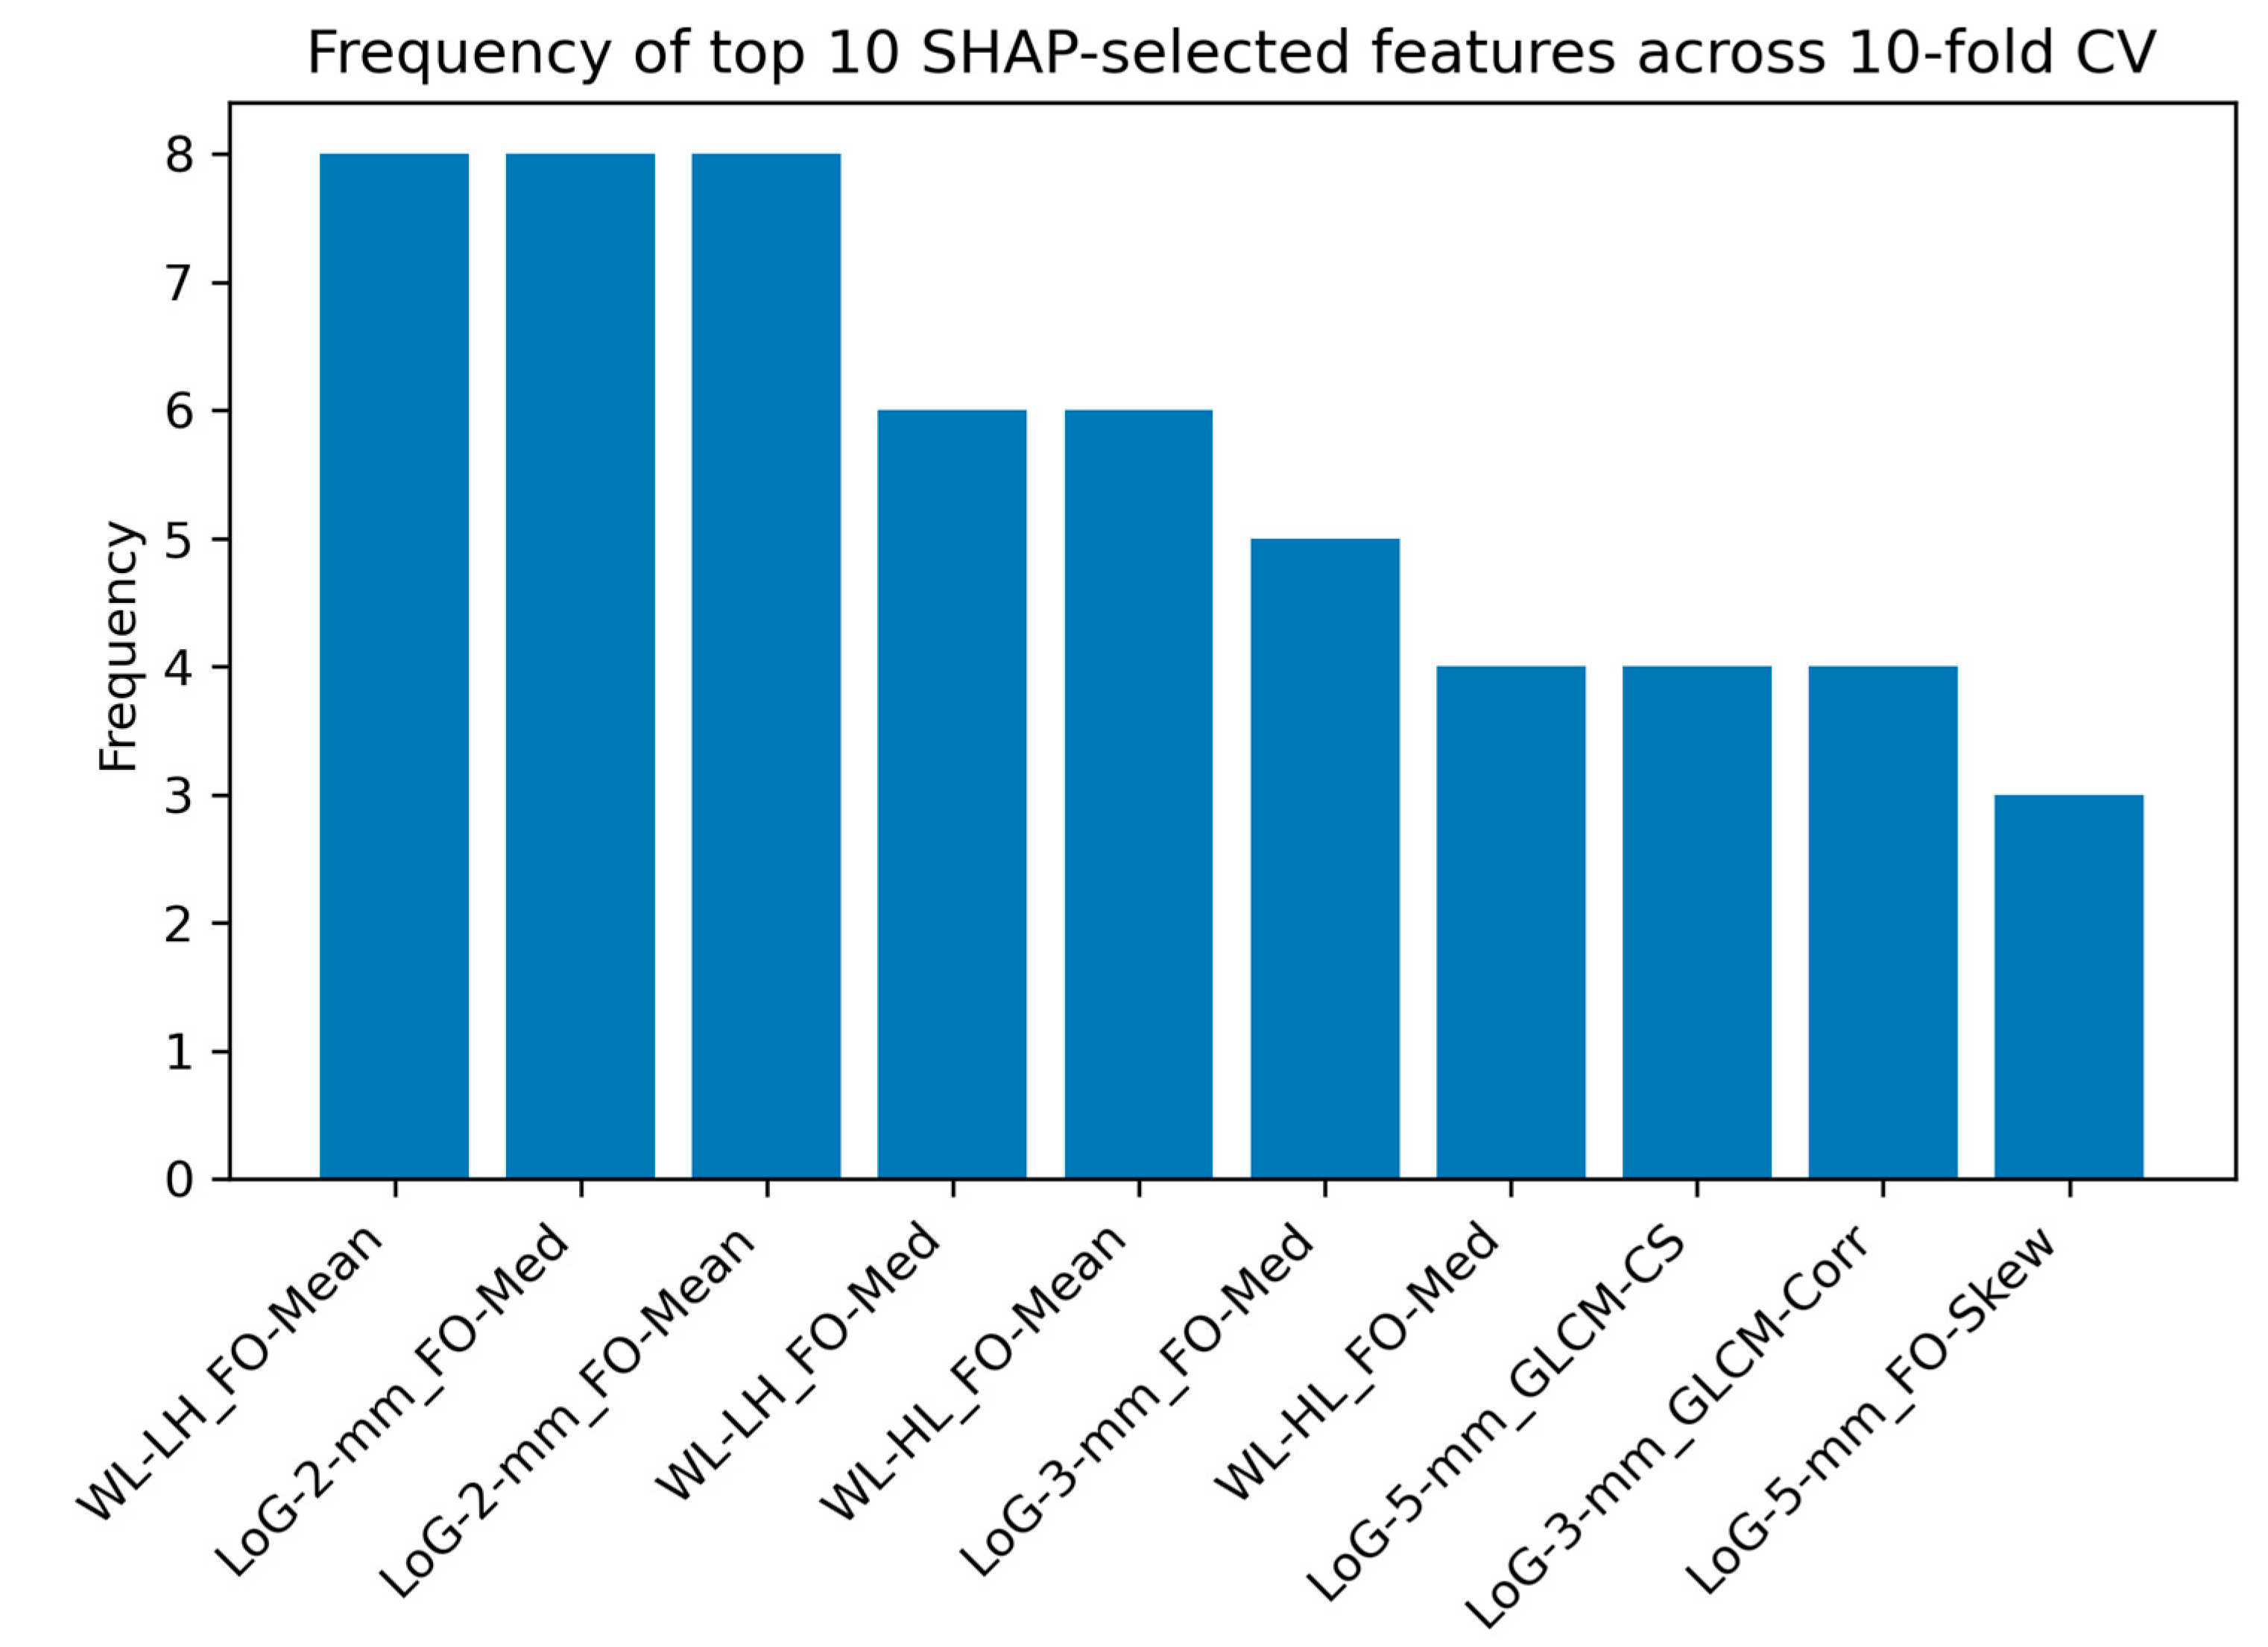

2.2.5. SHAP Analysis for Feature Interpretability

4.4. Interpretation of Radiomic Features Using SHAP Analysis